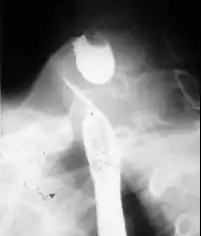

![]() Radiologiczny obraz uchyłka po połknięciu kontrastu | |

Rozpoznanie uchyłku opiera się na zdjęciu RTG po podaniu kontrastu (papka barytowa) i badaniu endoskopowym górnego odcinka przewodu pokarmowego celem wykluczenia procesu nowotworowego.